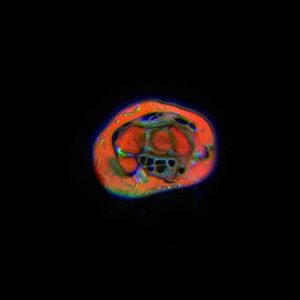

The narrowest section of the tunnel is located a centimetre beyond the mid-line of the distal row of carpal bones where the sectional area is limited to 1.6 cm2.[2]

Ten structures pass through the carpal tunnel, most of them flexor tendons[2] (not the muscles themselves):

- flexor digitorum profundus (four tendons)

- flexor digitorum superficialis (four tendons)

- flexor pollicis longus (one tendon)

- Median nerve between tendons of flexor digitorum profundus and flexor digitorum superficialis